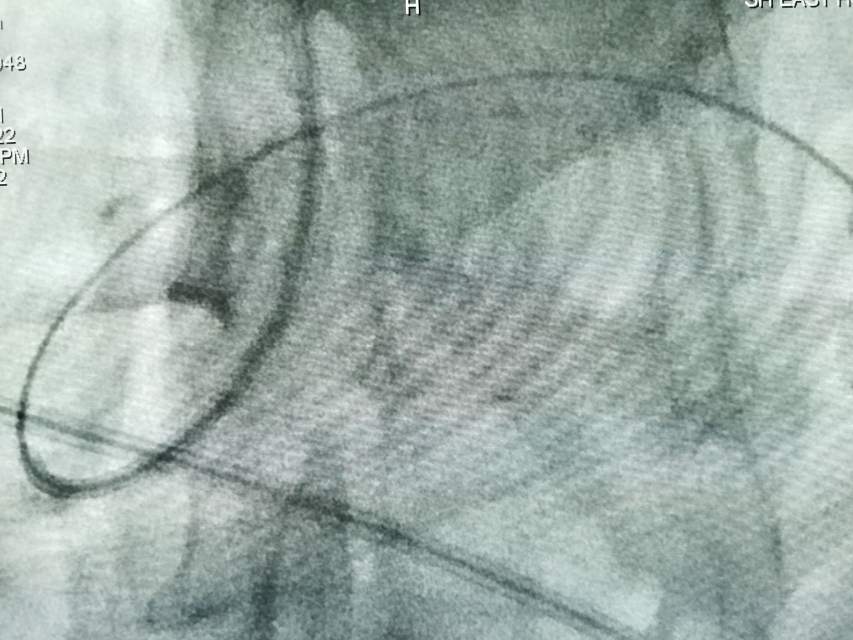

鉴于老人家体质虚弱,走路不方便,疫情期间,家人又不方便陪同,我们采用最微创的远侧桡动脉入路为老人家做了进一步检查,血管真的很扭哈,老人家也听不清楚,检查期间动来动去的,结果发现:下水道(深浅静脉系统有血栓堵塞)不通畅哦,次日给予了药物调整。治疗3天后,老人家听力明显改善,可以和医生自由交流,下床走路也如履平地,完全换了一个人哈~~~